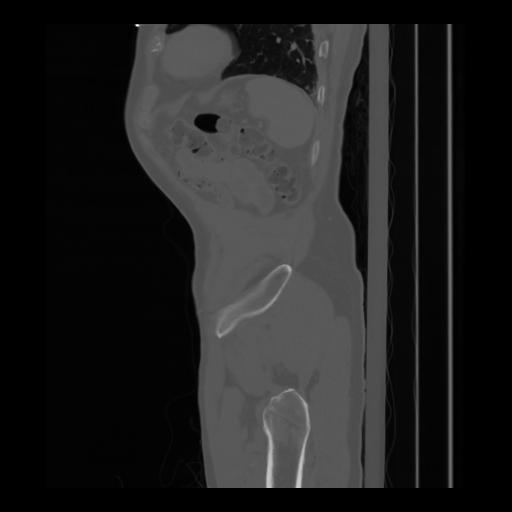

36 CUERPO,CE,Sagittal,3.000,CUERPO,Sagittal,